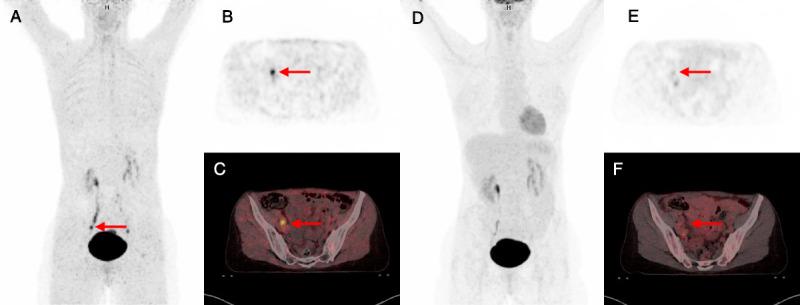

All 7 patients had focal uptake above background in their tumor lesions in [68Ga]Ga-FAPI-46 PET/CT. [68Ga]Ga-FAPI-46 PET/CT showed a higher tumor-to-background ratio (TBR) in primary tumor as well as in LN metastasis. Median TBRmax values using liver were 32.02 and 5.15 for [68Ga]Ga-FAPI-46 PET/CT and [18F]F-FDG PET/CT, respectively. Median TBRmax using blood pool was 18.45 versus 6.85 for [68Ga]Ga-FAPI-46 PET/CT and [18F]F-FDG PET/CT, respectively. Higher TBR also applies for nodal metastasis: TBRmax was 14.55 versus 1.39 (liver) and 7.97 versus 1.8 (blood pool) for [68Ga]Ga-FAPI-46 PET/CT and [18F]F-FDG PET/CT, respectively. Overall, [68Ga]Ga-FAPI-46 PET/CT detected more lesions compared with [18F]F-FDG PET/CT. Following surgical staging, a total of 5 metastatic LNs could be pathologically confirmed, of which 2 and 4 were positive by [18F]F-FDG PET/CT and [68Ga]Ga-FAPI-46 PET/CT, respectively.

7 名患者的肿瘤病变在 [68Ga]Ga-FAPI-46 PET/CT 中均显示出高于背景的局灶性摄取。[68Ga]Ga-FAPI-46 PET/CT 显示原发性肿瘤和 LN 转移中的肿瘤与背景比 (TBR) 更高。使用肝脏的中位数 TBRmax 值分别为 32.02 和 5.15,用于 [68Ga]Ga-FAPI-46 PET/CT 和 [18F]F-FDG PET/CT。使用血池的中位数 TBRmax 值分别为 18.45 和 6.85,用于 [68Ga]Ga-FAPI-46 PET/CT 和 [18F]F-FDG PET/CT。较高的 TBR 也适用于淋巴结转移:TBRmax 分别为 14.55 和 1.39(肝脏)和 7.97 和 1.8(血池),用于 [68Ga]Ga-FAPI-46 PET/CT 和 [18F]F-FDG PET/CT。总体而言,[68Ga]Ga-FAPI-46 PET/CT 比 [18F]F-FDG PET/CT 检测到更多的病变。在进行手术分期后,共可病理证实 5 个转移性 LN,其中 2 个和 4 个分别通过 [18F]F-FDG PET/CT 和 [68Ga]Ga-FAPI-46 PET/CT 呈阳性。